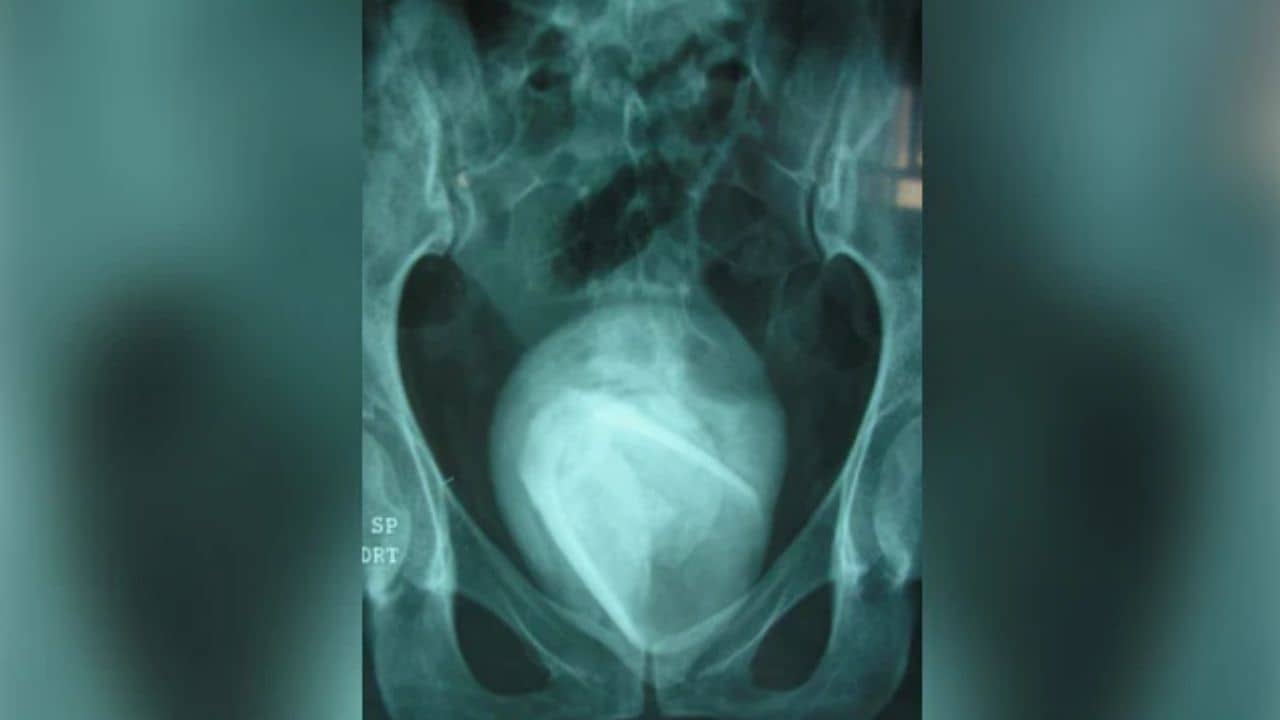

তিউনিসিয়া: ইউরিনারি ট্র্যাক্ট ইনফেকশনের আশঙ্কা করে এক মহিলা এক মহিলা ডাক্তারের কাছে গিয়েছিলেন। তার মূত্রজনিত বিভিন্ন সমস্যা দেখা দিয়েছিল এবং সবসময়ই শৌচালয়ের প্রয়োজন হত। চিকিৎসক ওই মহিলাকে দেখার পর তাঁকে বেশ কিছু পরীক্ষা করার নির্দেশ দিয়েছিলেন। চিকিৎসকের পরামর্শ মত ওই মহিলা তারা ব্লাডারের স্ক্যান করেন। স্ক্যান রিপোর্ট আসার পর ওই মহিলা ও সংশ্লিষ্ট চিকিৎসক রীতিমতো চমকে গিয়েছেন। স্ক্যান রিপোর্টে জানা গিয়েছে, তার ব্লাডারে দীর্ঘ ৪ বছর ধরে একটি কাচের গ্লাস আটকে ছিল।

ব্লাডারের স্ক্যানের পর জানা দেখা গিয়েছে, ওই মহিলার দেহে কাচের গ্লাসের পাশাপাশি একটি বড় পাথরও রয়েছে। এবং দেহের বিচারে পাথরটির আকার বৃহৎ এবং চওড়ায় ওই পাথরটি ৮ সেমি। এখনও অবধি ওই মহিলার পরিচয় প্রকাশ করা হয়নি। এই বিষয়ে মার্কিন সংবাদমাধ্যম ‘নিউ ইয়র্ক পোস্ট’-এ প্রতিবেদন প্রকাশিত হয়েছে। ওই সংবাদমাধ্যমের মতে ওই মহিলা চিকিৎসকদের জানিয়েছেন, চার বছর আগে তিনি যৌন চাহিদা মেটাতে ওই কাচের গ্লাসটি ব্যবহার করেছিলেন। এবং যৌন উত্তেজনার মুহূর্তে নিজের অজান্তেই যোনির পরিবর্তে মূত্রনালিতে তিনি ও কাচের গ্লাসটি ঢুকিয়ে ফেলেছিলেন। সায়েন্ট ডাইরেক্ট নামক একটি মেডিক্যাল জার্নালেও এই মহিলার ঘটনাটি প্রকাশিত হয়েছে।

ওই মেডিক্যাল জার্নাল জানিয়েছে, এর আগেও এই ধরনের অনেক ঘটনার উদাহরণ রয়েছে। যৌন চাহিদা মেটাতে অনেকেই বিভিন্ন বস্তুর আশ্রয় নিয়েছে, এবং সেই গুলি বের করে আনা সম্ভব হয়নি। এই বিষয়গুলি এতটাই অস্বস্তিদায়ক যে তারা চিকিৎসকের পরামর্শও নেননি। ফলে স্বাভাবিকভাবেই সেই থেকে সংক্রমণ ছড়িয়ে পড়েছে। তিউনিসিয়ার শহরের হাবিব বুরগুইবা বিশ্ববিদ্যালয় হাসপাতালের চিকিৎসকরা শল্য চিকিৎসার সিস্টোলিথোটমি পদ্ধতি ব্যবহার করে ওই মহিলার ব্লাডার থেকে কাচের গ্লাসটি বের করেছেন। চিকিৎসকরা জানিয়েছে, ওই মহিলার মূত্রে রক্ত পাওয়া যায়নি।